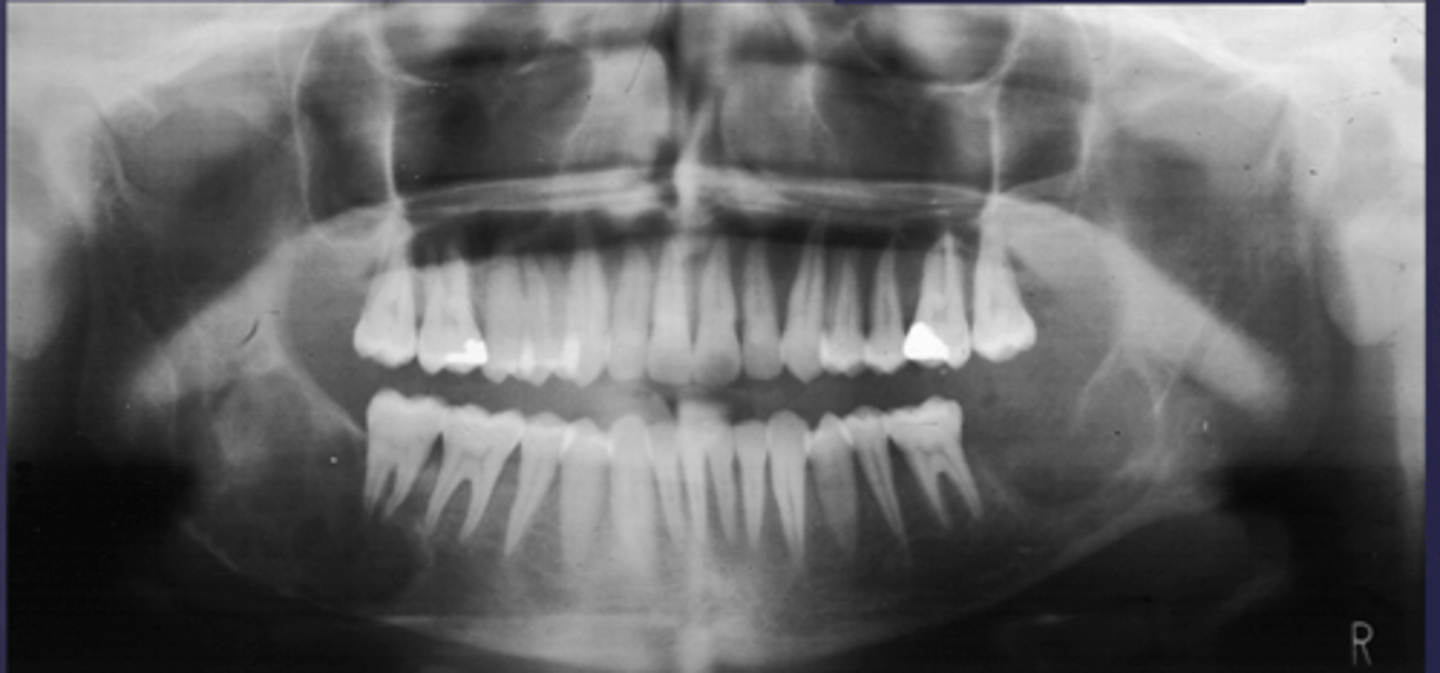

How would you describe the lesion?

- Periapical radiolucency associated with #30

- Has a band of sclerotic change extending from the apical radiolucency to the inferior alveolar canal and beyond

- Furcation involvement

(Furcation involvement as well as a band of sclerotic change extending from the apical radiolucency to the inferior alveolar canal and beyond)

What category would you put this lesion into?

Inflammation

what could be a differential diagnosis for this lesion? (select all that apply)

A. PCOD

B. multiple myeloma

C. apical rarefying osteitis

D. chronic sclerosing osteomyelitis

Also note apical rarefying osteitis #14 ( remnant root fragments, no crown due to caries)